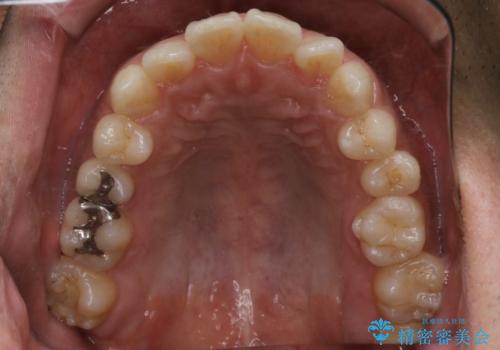

- 上下の前歯のがたつきが気になるとご相談にいらした方です。光加速矯正装置(オルソパルス)を用いて短期間で仕上げることが出来ました。

一般的に噛む力が強い方は矯正治療に時間がかかると言われてます。光加速矯正装置(オルソパルス)を用いることで短期間で仕上げることができました。